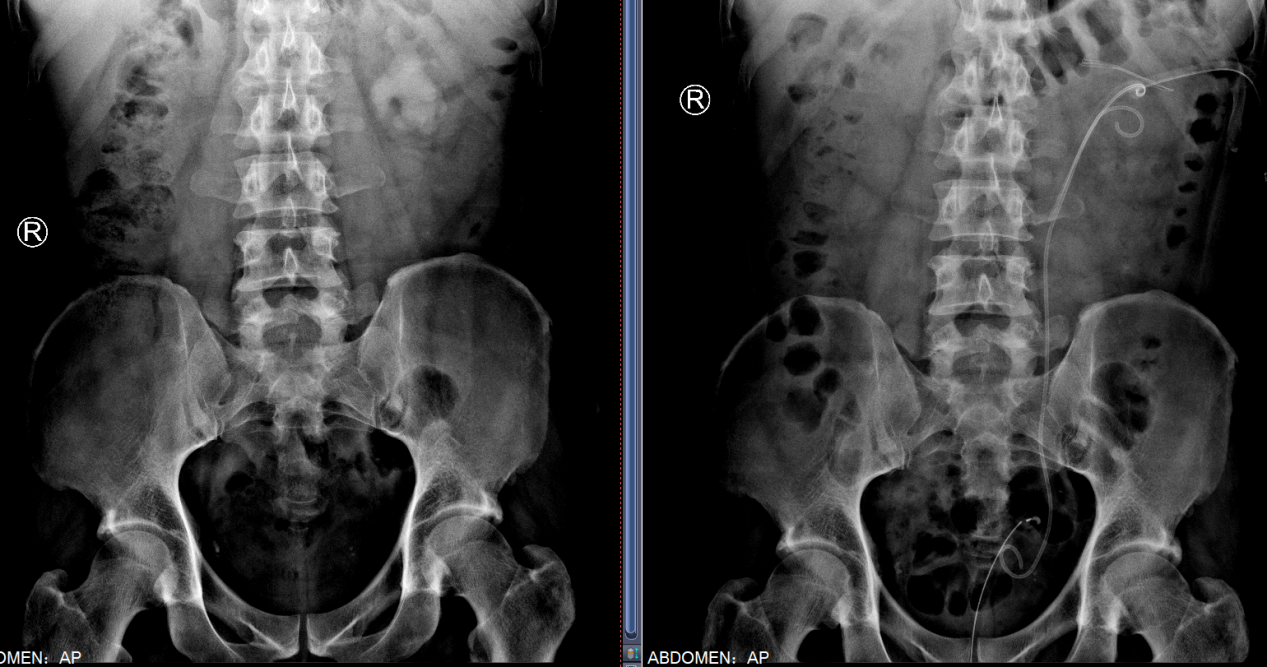

术中,周守军主任医师选择肾脏中盏背侧后组为穿刺路径,超声实时引导下,精准穿刺至目标肾盏,整个穿刺过程一气呵成,通过F20单通道配合第五代EMS(瑞士EMS超声弹道碎石系统)一次性完成超声碎石取石手术,术后复查无明显结石残留。通过此次手术,医生借由一个大小仅7mm的切口,就彻底清除了左侧肾内6.8cm大的结石,解除了困扰患者2年多的烦恼,患者对手术结果表示非常满意。

术后,在刘雪护士长团队的精心护理下,患者术后5天拔除造瘘管,1周顺利出院。